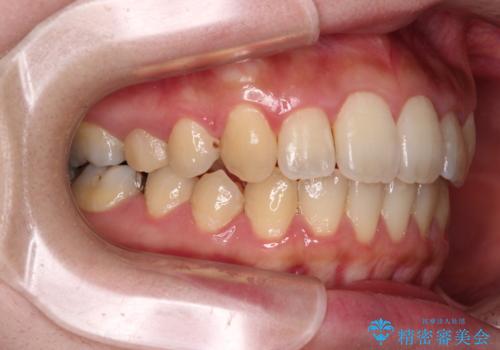

- 捻れた前歯が飛び出しており、口が閉じにくいとのことで来院された患者様です。

出っ歯というわけではないものの、前歯の捻転により口唇が押し出されている状態でした。

親知らずを抜去し、歯列全体を後方に移動させつつ、IPR(歯と歯の間を削る)でスペースを獲得し、インビザラインを用いて叢生を解消しながら前歯の突出を改善することとしました。

インビザラインは、患者様の協力無しには成立しない治療ですが、しっかりと装着時間を遵守してくださり、1年弱で治療を終えることができました。